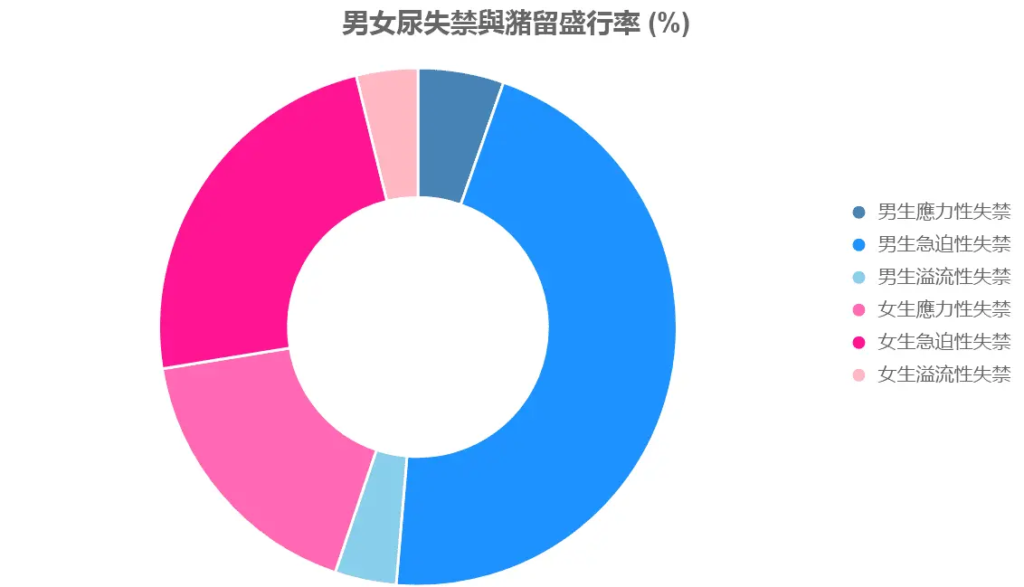

統計數據圖表:尿失禁與潴留盛行率(%)

使用表格展示全球數據:

| 类型 | 男生盛行率 (%) | 女生盛行率 (%) | 主要原因 |

|---|---|---|---|

| 應力性失禁 | 3-11 | 11-34 | 肌鬆弛/分娩 |

| 急迫性失禁 | 40-80 (男性總) | 31 (75歲以上) | 激素/神經 |

| 溢流性失禁 | 5 | 5 | 潴留/阻塞 |

| 總失禁 | 5.5 | 11.2 | 解剖/激素 |

數據顯示,女生失禁率為男生的2倍。

尿失禁與潴留盛行率

描述:

此圓環圖展示男女尿失禁與尿潴留的盛行率(%),分為應力性失禁、急迫性失禁與溢流性失禁:

- 男生(藍色系):應力性3-11%,急迫性40-80%,溢流性5%。

- 女生(粉紅系):應力性11-34%,急迫性31%,溢流性5%。

原因分析:

圓環圖顯示,女生應力性失禁盛行率(22.5%)遠高於男生(7%),因分娩與雌激素影響。急迫性失禁在老年男性中較高(前列腺問題),而女生總失禁率(11.2%)為男生的2倍。